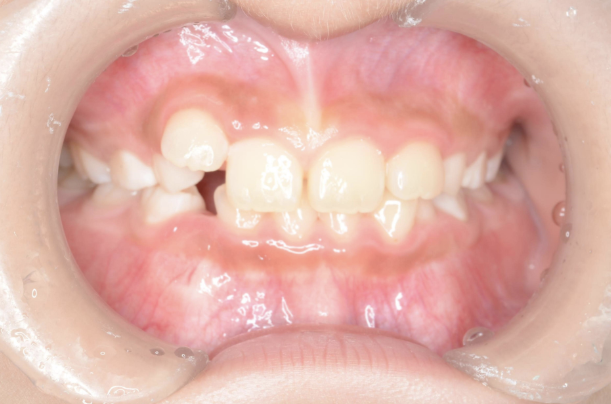

お子さんが「矯正治療」をはじめる時に直面する問題は 「装置が目立つ」、 そして「歯を抜く」ことがあげられます。

10歳を超えてからの治療開始ではそのようにならざるを得ないことが多いのです。

しかしながら、5〜7歳頃に治療をスタートすれば 目立ちにくい装置で、歯を抜かずに治療できることがあります。

10歳を過ぎてからの矯正治療の場合、大人の歯を抜いて治療することが多くなります。 一方、下の前歯が生えてくる5〜7歳頃から治療を始めると、大人の歯を抜かずに治療することが可能です。 抜かずに治療するには早期に治療を開始することが大切です。

歯並びが悪いのは、あごの骨が成長不足で小さいことで起こります。 当院で行なっているこどもの歯ならび治療はあごの骨に働きかけることができます。 骨に働きかけることで成長不足のお子さんの骨が成長して、顔つきが良い方向に変わっていく可能性があります。 実は大きくなってからの矯正治療は歯が並んでいるだけで骨やお顔つきは変わっていないのです。 5〜7歳ぐらいで治療を開始すると成長不足の骨に働きかけて、より良い顔つきになれる可能性があります。